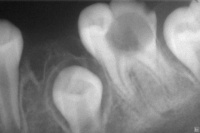

2.检查牙体硬组织色、形、质的改变,龋坏的部位、深度和类型。注意邻面、颈部或牙龈遮盖部位的龋洞。必要时可摄X线照片检查。

临床上可见龋齿有色、形、质的变化,而以质变为主,色、形变化是质变的结果,随着病程的发展,病变由釉进入牙本质,组织不断被破坏、崩解而逐渐形成龋洞,临床上常根据龋坏程度分为浅、中、深龋三个阶段。

浅龋:亦称釉质龋,龋坏局限于釉质。初期于平滑面表现为脱矿所致的白垩色斑块,以后因着色而呈黄褐色,窝沟处则呈浸墨状弥散,一般无明显龋洞,仅探诊时有粗糙感,后期可出现局限于釉质的浅洞,无自觉症状,探诊也无反应。

中龋:龋坏已达牙本质浅层,临床检查有明显龋洞,可有探痛,对外界刺激(如冷、热、甜、酸和食物嵌入等)可出现疼痛反应,当刺激源去除后疼痛立即消失,无自发性痛。

深龋:龋坏已达牙本质深层,一般表现为大而深的龋洞,或入口小而深层有较为广泛的破坏,对外界刺激反应较中龋为重,但刺激源去除后,仍可立即止痛,无自发性痛。

龋坏在X线片上呈黑色透射区,对难以确诊者(如邻面龋),可借助X线片协助诊断。

1) 浅龋 病变仅局限于牙釉质或牙骨质,局部可见白色或灰黑色的龋斑。无自觉症状,探查时可卡住探针尖端,探针滑过病变部位有粗糙感,探之无痛苦。

2) 中龋 病变较深,累及牙本质浅层,局部变黑,可有温度或化学性激发痛,探之有明显龋洞且敏感。

3) 深龋 病变深及牙本质深层而接近牙髓腔,遇食物嵌塞或冷热酸甜等刺激均产生疼痛,局部多见黑洞。探针可探查洞底在牙本质深层,探之极敏感或疼痛,无自发痛史。

2.辅助检查

若确定龋坏部位有困难,可拍摄X线牙片,龋坏处可见黑色阴影。有条件者可用光纤维透照、电阻抗、超声波、弹性模具分离、染色等技术,以提高龋病早期诊断的准确性和灵敏性。